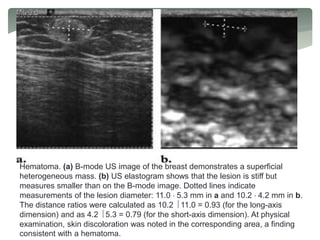

MRE of an inclusion phantom

(a) MR magnitude image of an inclusion phantom with soft and stiff inclusions

seen as the hyperintense and hypointense regions, respectively.

(b) A single wave image from the MRE acquisition performed at 100 Hz. The

difference in the wavelengths in the different regions is evident.

(c) An elastogram obtained from these data showing the stiff and soft regions.